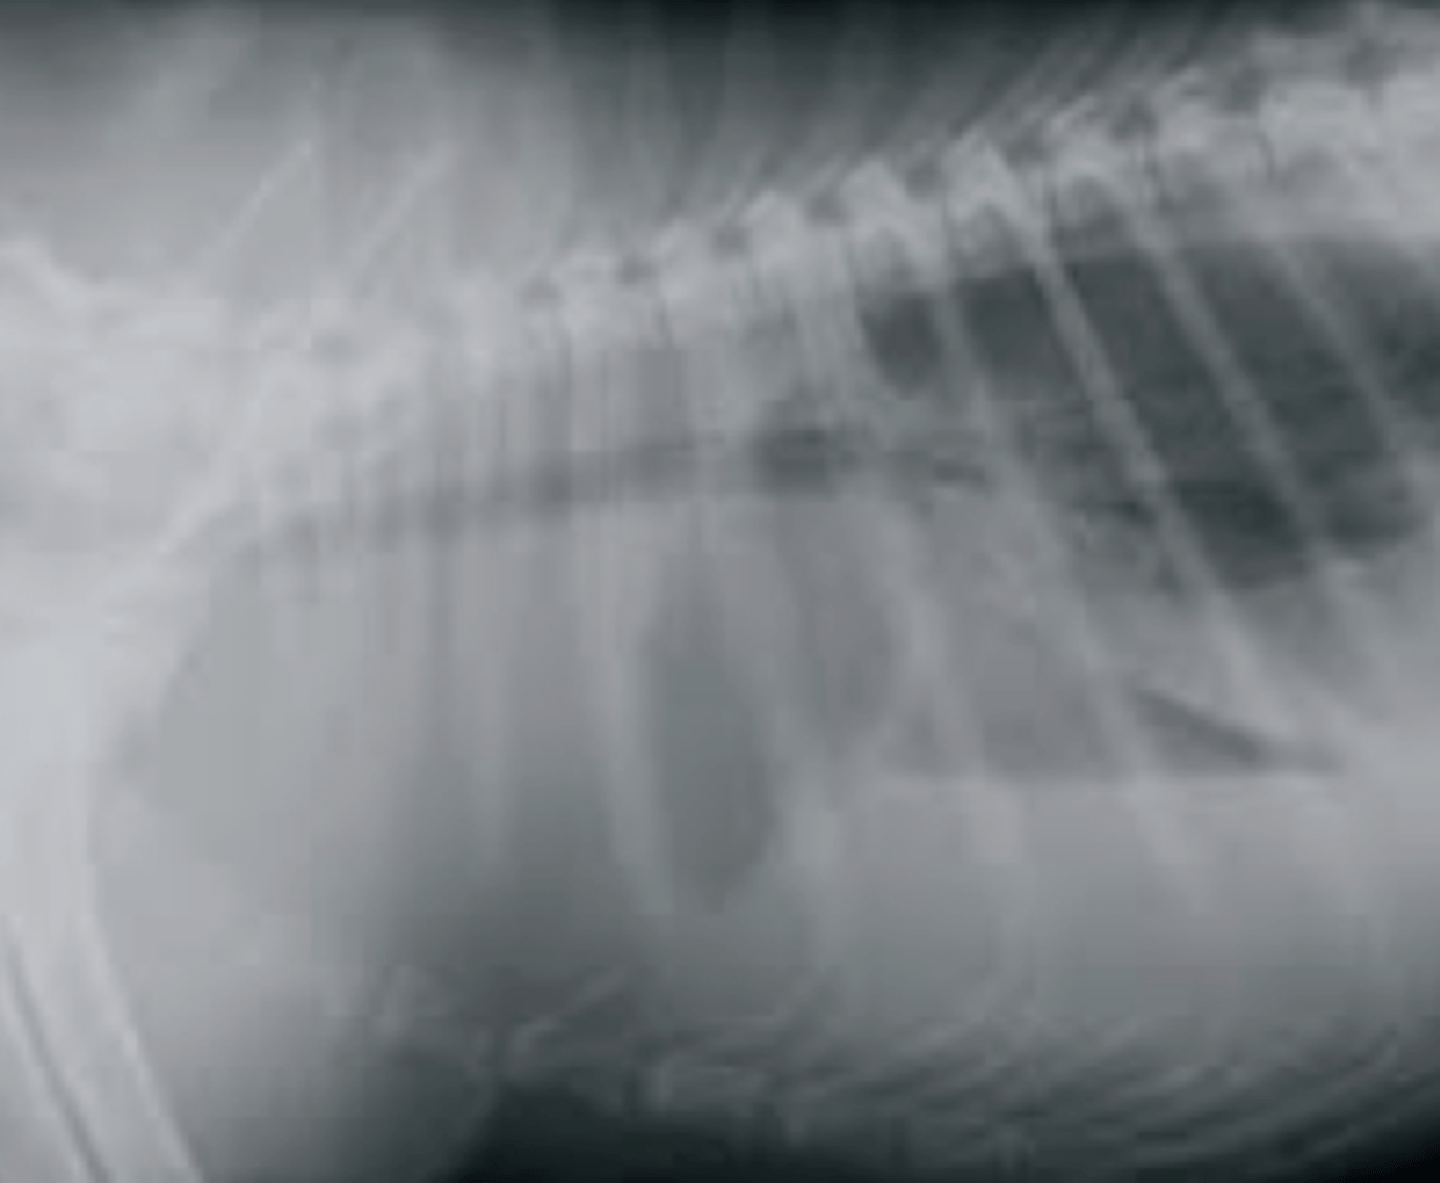

dilatación-torsión gástrica

patología: